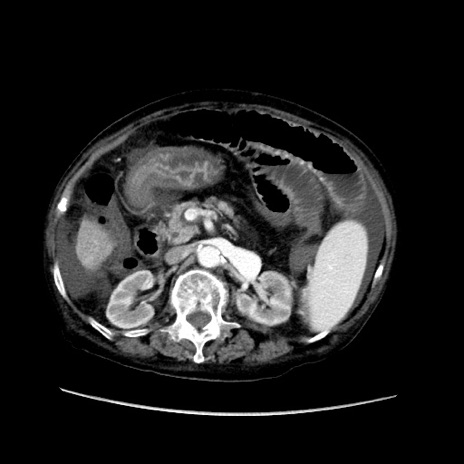

症例31(横断像)

【症例】80歳代 女性

【主訴】腹部膨満感

【現病歴】他院にて肝硬変にてフォロー中。1週間前から便秘、腹部膨満感、臍部腫瘤あり受診となる。

【既往歴】肝硬変

【身体所見】腹部膨隆あり、皮膚変化なし、疼痛なし。

【データ】WBC 4600、CRP 0.25